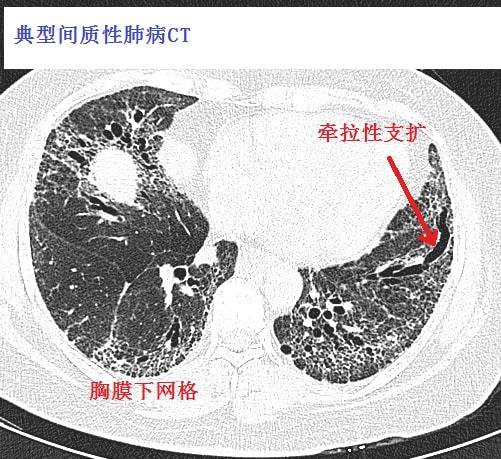

间质性肺炎的典型图谱,最全解析!

极易漏诊的间质性肺炎,从ct上怎么看?

间质性肺炎ct表现

间质性肺炎ct

间质性肺炎ct图片

间质性肺炎ct图片特点

间质性肺炎早期ct图片